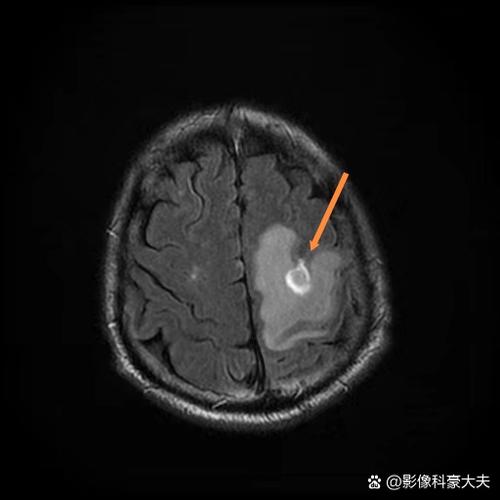

- 出血性转化: 这是指脑梗塞后,由于缺血坏死的血管破裂,导致梗塞灶内出现少量出血,在CT上,它会表现为在低密度梗塞灶内出现高密度出血影,这种情况CT是可以发现的,但诊断的初始目的已经从“排除梗塞”变成了“明确并发症”。